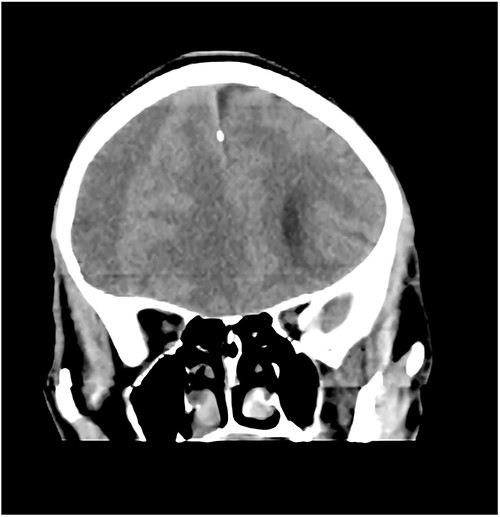

Prior to this, he had been managed for low back pain and lumbar spondylosis. Spine MRI done prior to neurosurgery consultation did not explain the lower extremity motor weakness. Brain CT done revealed bilateral fronto-parietal CSDH (Fig. 2A). He was worked up for urgent surgical evacuation through a bilateral frontal and parietal burr hole drainage. He made good neurologic improvement and his lower extremity power returned to normal on the 8th day post op. Post-operative CT scan done at 4 weeks follow-up showed satisfactory resolution of the haematoma (Fig. 2B).

(A) Pre-op showing bilateral CSDH. (B) Post op complete resolution of CSDH.